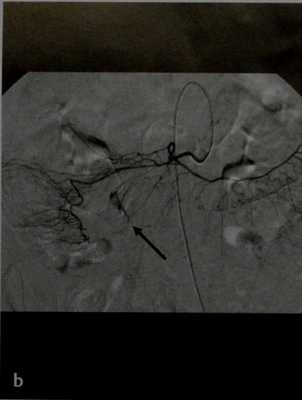

а, b Острое вытекание контрастного вещества в петлю подвздошной кишки (а) у пациента с множественными аневризмами сосудов брыжейки и печеночной артерии (стрелки на b).

а, b Кровотечение из дивертикула: а) КТ. Острое вытекание контрастного вещества в просвет поперечной ободочной кишки;

b) При ангиографии видно подтекание контрастного вещества (стрелка).